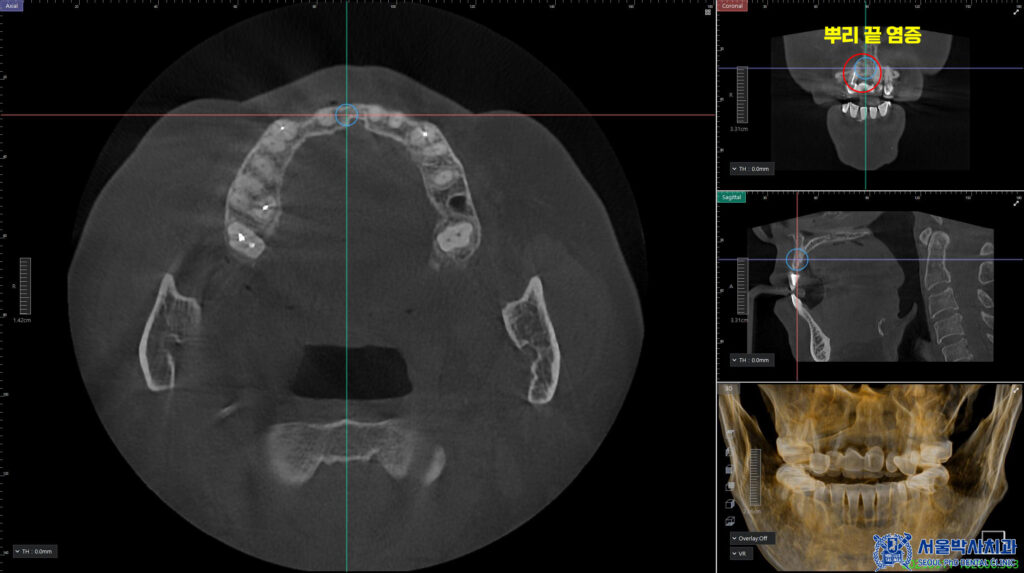

확인해 보니,

앞니 브릿지 일부가 파절 되어있었으며

보철물 안쪽의 충치와

CT상에서 뿌리 끝 염증이 있었습니다.